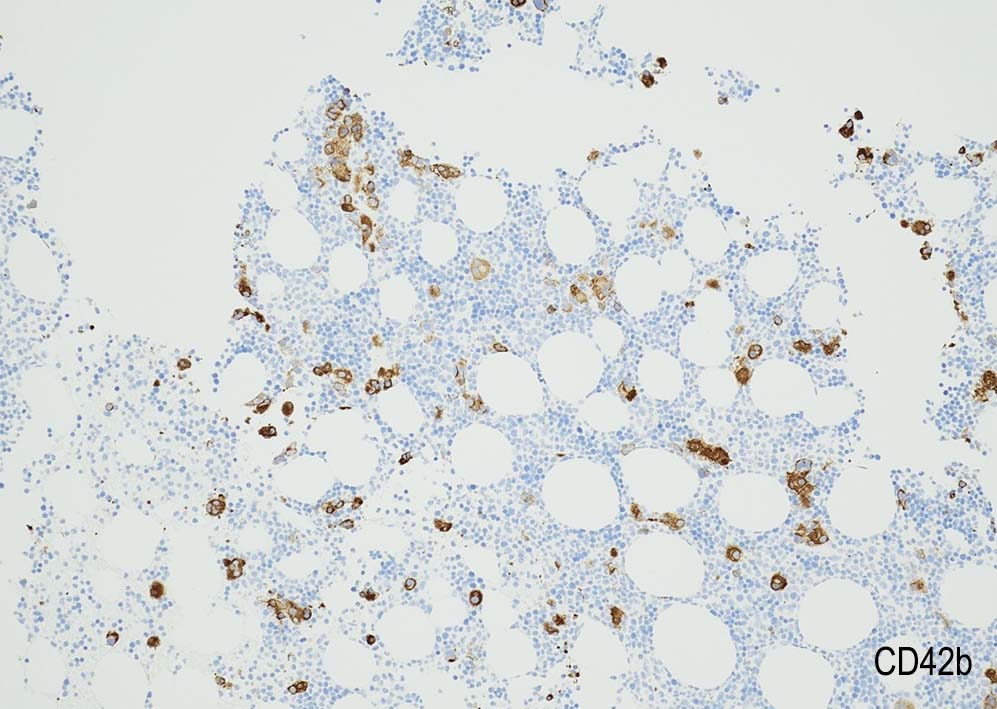

80歳代男性. 徐脈で治療中, 末梢血で血球異形成を指摘される. Hb8.8g/dl, RBC 402x104/μl, MCV 76, WBC 2500/μl, Plt. 3.9x104

Megakaryopoiesis; Mgkは増加している. 多数の分離円形核巨核球が出現している. microMgkが増加している.

Myelogram: M/E = 1.77,Blast-M 5.2%, promyelo 7.0%, Myelo 11.4%, Meta 10.0%, Stab 5.4%, Seg 18.8%, Eo mature 0.6%, Ba mature 0.6% Mo 3.0%, Lympho 4.4%, Plasma 0.2 骨髄WT1 R 1.1x104